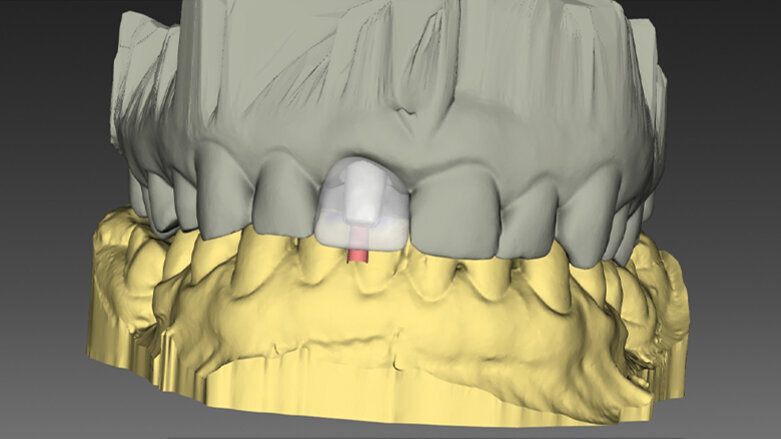

Plánování tvaru a velikosti budoucí CAD/CAM e.max korunky v programu In Lab 16 na základě obdrženého souboru Core File. (fotografie: Lek. Dent Michal Nawrocki)

Plánování tvaru a velikosti budoucí CSD/CAM e.max korunky v programu In Lab 16 na základě obdrženého souboru Core File.

Po naplánování pozice implantátu a budoucí korunky byla všechna data odeslána do Belgie s cílem vyrobit chirurgickou šablonu. Když byla chirurgická šablona navržena, byly soubory odeslány do frézovacího centra ATLANTIS ve Švýcarsku s cílem vytvořit individuální abutment. Po schválení virtuálního projektu abutmentu byl během hodiny vytvořen a bezprostředně odeslán na kliniku soubor, tzv. Core File. Díky tomu zubní technik mohl naplánovat a vyfrézovat dočasnou korunku v systému CAD/CAM Sirona CEREC. Tato šroubovaná korunka bez okluzních kontaktů byla zhotovena z bločku keramiky e.max a na individuální abutment Atlantis Custom Base (s povrchem TiN) byla nacementována mimo dutinu ústní. Všechny komponenty – chirurgická šablona SIMPLANT, abutment Atlantis Custom Base i dočasná korunka, byly zhotoveny před chirurgickým výkonem.